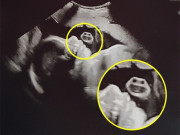

Đây là những lưu ý quan trọng cho bố mẹ đang trong hành trình "thả bầu" chuẩn bị đón con yêu.

Hành trình tìm kiếm một em bé không phải lúc nào cũng diễn ra nhanh chóng như nhiều người kỳ vọng. Trên thực tế, không ít cặp vợ chồng rơi vào trạng thái căng thẳng khi đã cố gắng trong vài tháng nhưng vẫn chưa có kết quả.